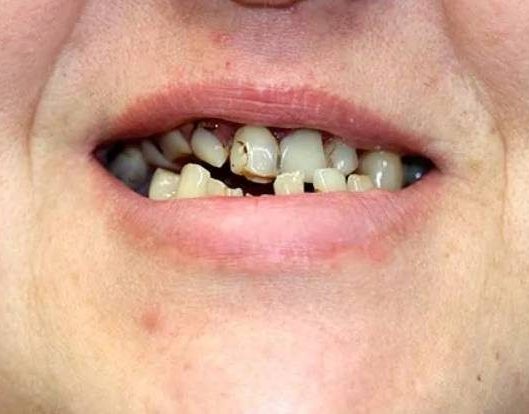

All-on-4® — рациональный выбор пациентов как с полной адентией, так и частичной. Первые устали от съемных протезов, вторые — измучены лечением последних оставшихся во рту зубов и желают никогда больше не знать зубной боли. Концепция решает накопившиеся проблемы пациента радикально, раз и навсегда

Через 5 лет ношения съемных протезов

Примеры работ до и после имплантации All-on-4

Здоровые зубы и отзывы наших пациентов

до и после имплантации All-on-4